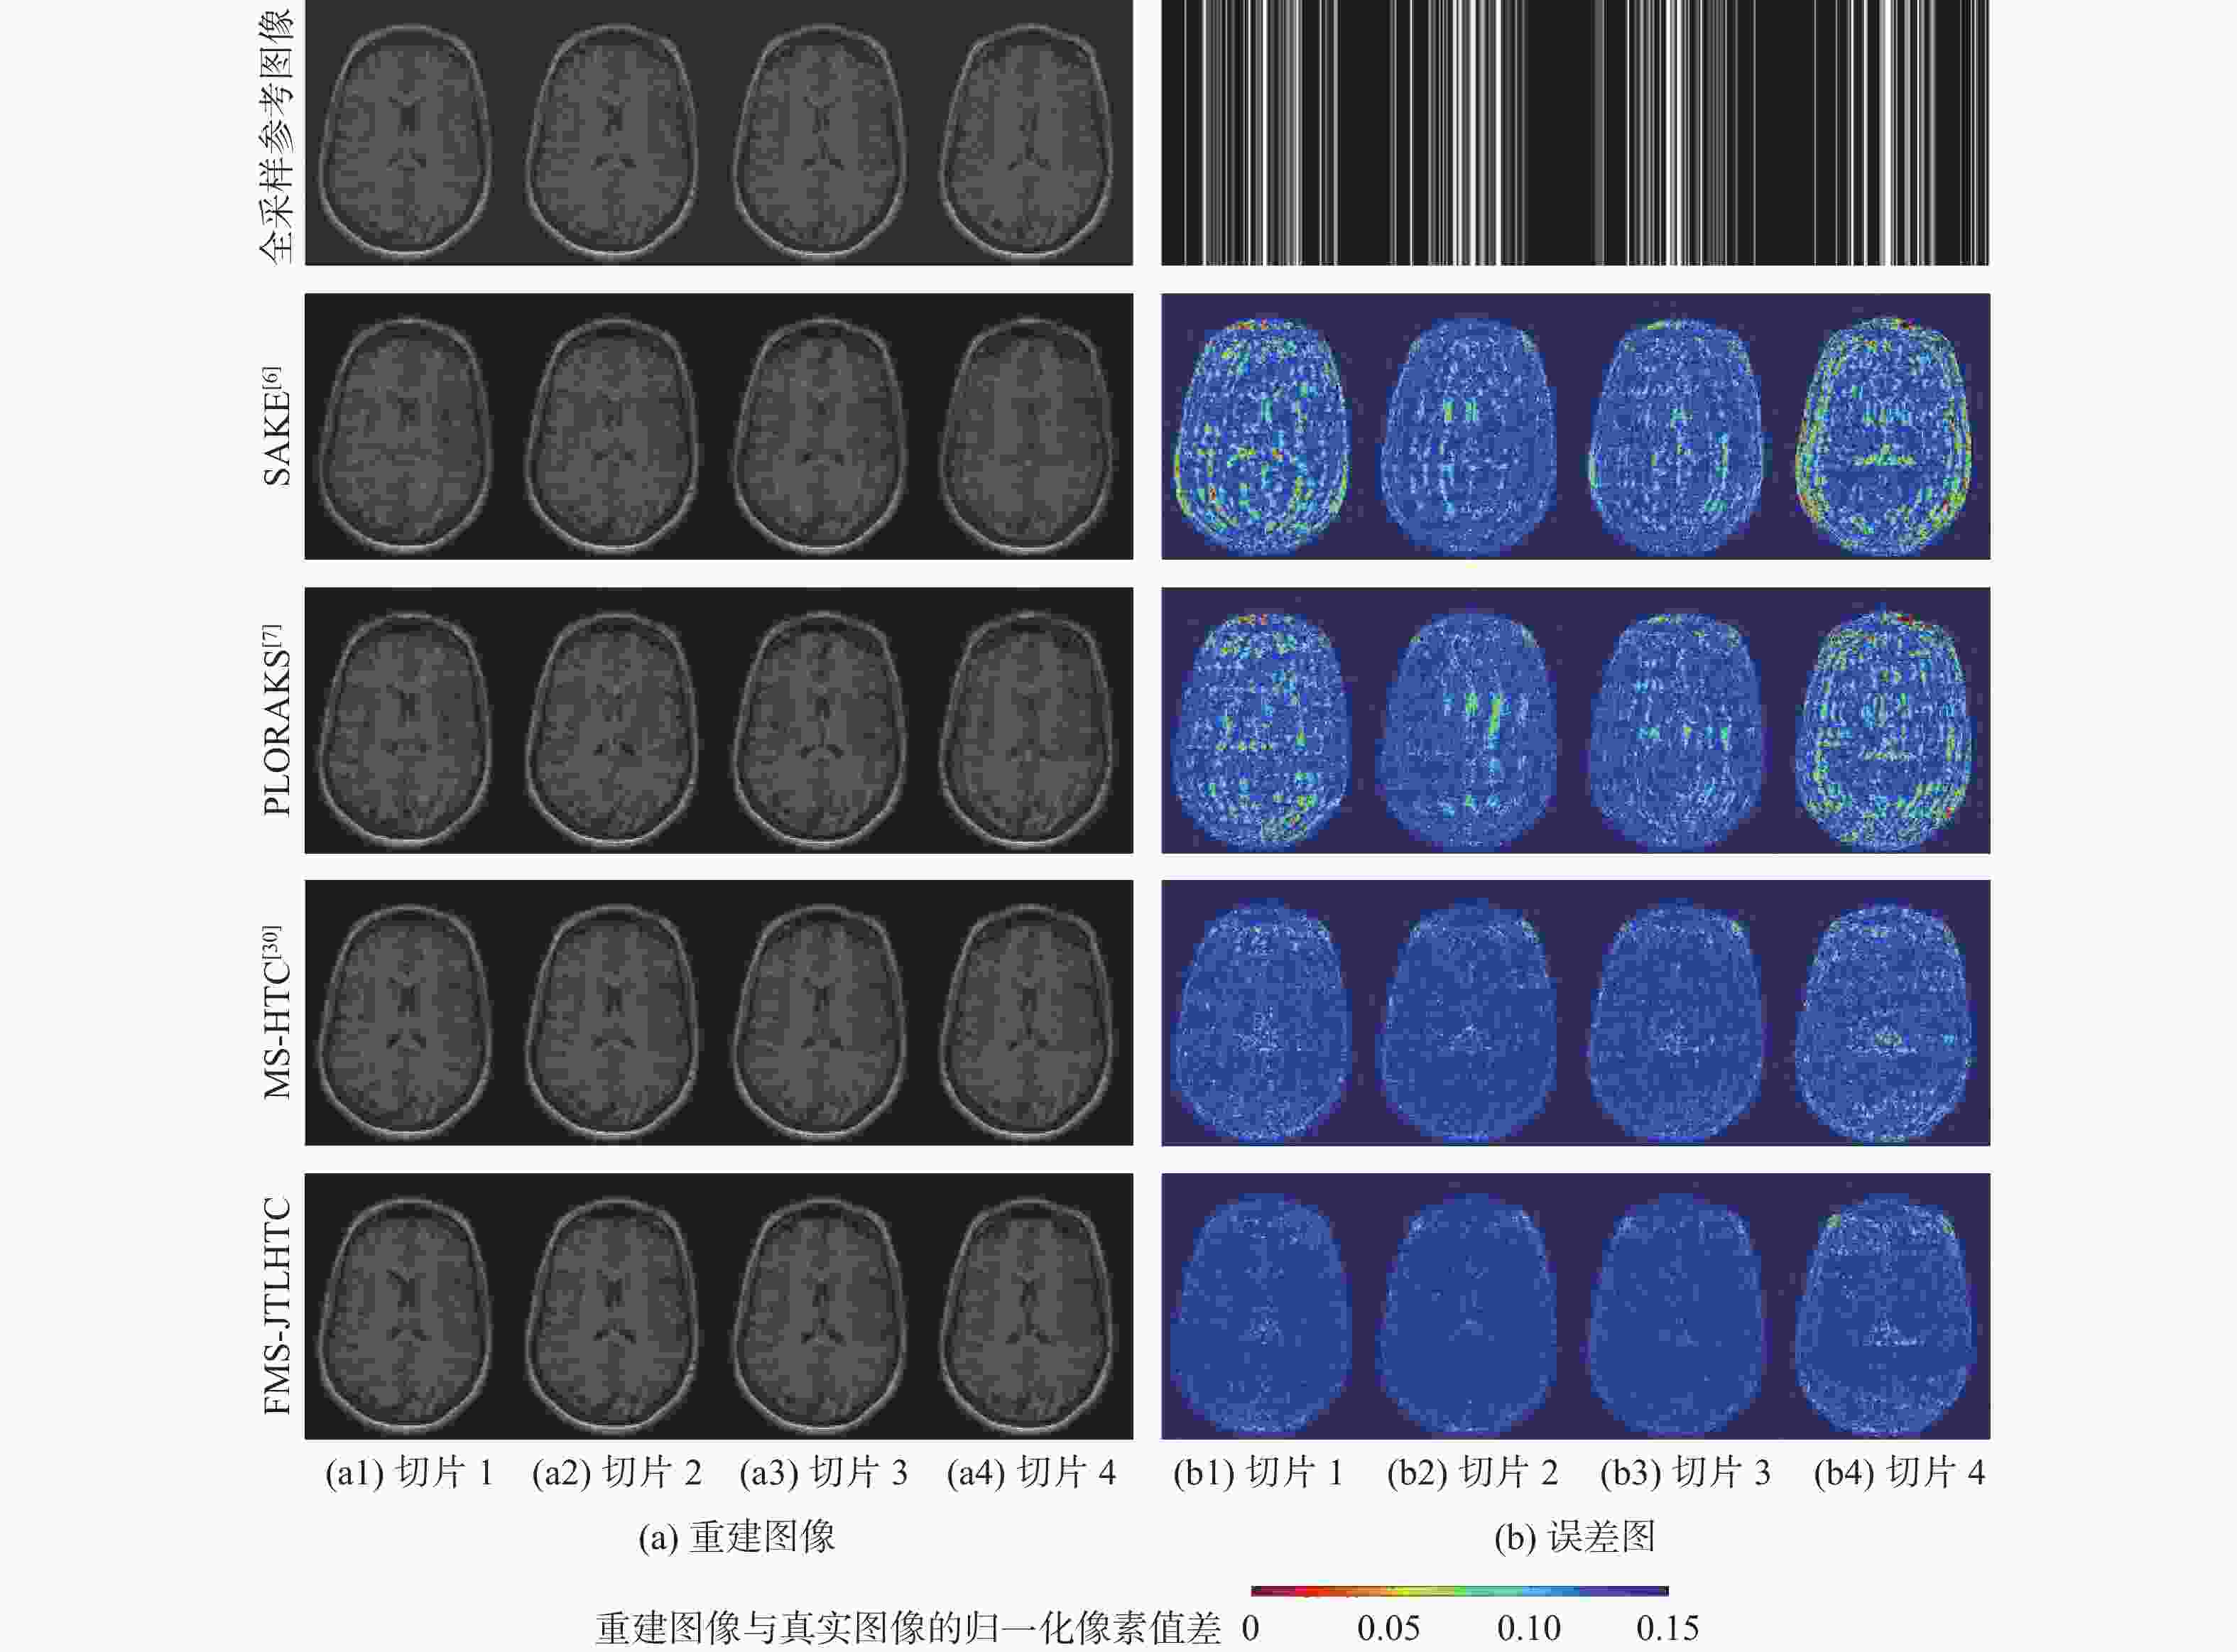

二维(2D)多切片磁共振数据在相邻切片之间具有高度的相关性,通过利用切片间的冗余性能够重建出更高质量的切片图像,但由于硬件条件的限制,2D多切片磁共振成像(MRI)需要耗费大量时间。为提高2D多切片磁共振图像的重建质量和重建速度,将联合稀疏变换学习正则项引入到多切片Hankel张量完成(MS-HTC)模型中,提出一种快速2D多切片磁共振成像重建(FMS-JTLHTC)算法。该算法使用交替方向乘子法对目标问题进行求解;引入快速迭代收缩阈值法加快收敛,并使用图形处理器对算法进行加速。使用4组脑部数据集在2种不同采样模式下进行实验,结果表明:FMS-JTLHTC算法的峰值信噪比(PSNR)相较于同时自动校准和K空间估计(SAKE)算法、并行成像数据的局部K空间领域的低秩建模(PLORAKS)算法和MS-HTC算法分别平均提高了4.04 dB、3.67 dB和2.07 dB,而且重建速度相比MS-HTC算法提高了14倍。

Abstract:Due to the significant correlation between neighboring slices in two-dimensional (2D) multi-slice magnetic resonance data, higher quality slice pictures can be reconstructed by taking use of the redundancy between slices. However, 2D multi-slice magnetic resonance imaging requires an amount of time. To improve the reconstruction quality and speed of 2D multi-slice (MRI) images, proposes a fast 2D multi-slice MRI reconstruction (FMS-JTLHTC) algorithm, which introduces the joint transform learning regular term into the multi-slice hankel tensor completion (MS-HTC) model. Prior to introducing the fast iterative shrinkage-thresholding procedure to accelerate convergence and utilize the graphics processing unit to speed up the procedure, the alternating direction method of multipliers is used to solve the objective issue. Experiments using four brain datasets in two different sampling modes show that the peak signal-to-noise ratio (PSNR) of the FMS-JTLHTC algorithm is improved by an average of 4.04 dB, 3.67 dB, and 2.07 dB compared to the simultaneous atuo-calibrating and K-space estimation (SAKE), low-rank modeling of local K-space neighborhoods with parallel imaging data (PLORAKS) and MS-HTC algorithms, respectively, the reconstruction speed is improved by a factor of 14 compared to the MS-HTC algorithm.